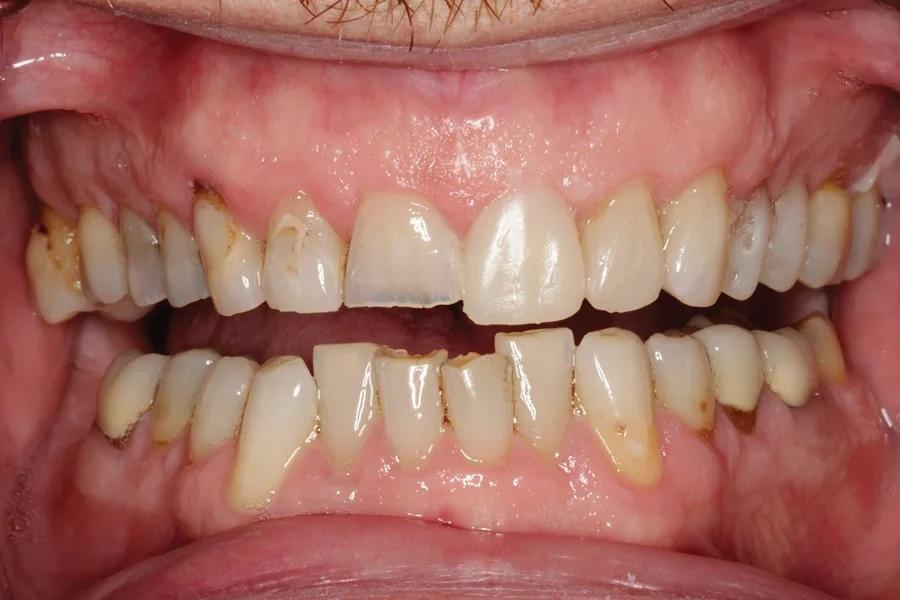

Мужчина, 45 лет. Основная жалоба — неловкость при улыбке из-за коротких, деформированных и измененных в цвете зубов. Обследование выявило гингивит с соответствующей потерей прикрепления, множественные кариозные поражения, износ зубов и реставраций (Фото 1 – Фото 3). Зафиксирован ограниченный паттерн жевания (ОПЖ), что определило умеренный функциональный риск и необходимость учета окклюзии в плане лечения.

Фото 2. Улыбка крупным планом до лечения.